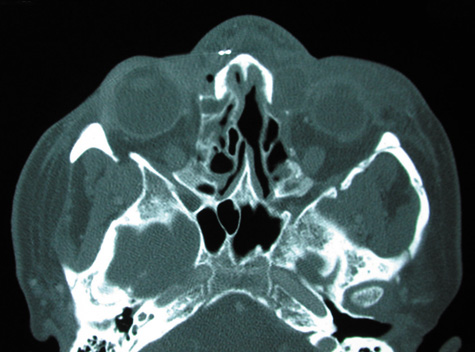

CT should be performed using thin-section (2–4 mm) high-resolution scanning with multiple views of both bone and soft tissue detail.53 Axial and coronal views should be obtained; in one-third of patients with subperiosteal abscesses, the abscess was seen in the coronal sections only.18 Helical CT is a fairly new technology that allows increased resolution with decreased imaging time.60 This type of scan may be especially beneficial in children because of the ability to obtain good imaging with a shorter imaging time.60 elica He HhIntravenous contrast material is not advocated at all centers because there is intrinsically high contrast between infectious changes and orbital fat. However, some authors believe that it is essential to the diagnosis, and it thus remains the preference of the individual clinician, as well as the neuroradiologist.22,59,62

CT is particularly useful for imaging orbital and subperiosteal abscesses. Because the periorbit is not adherent to the orbital walls except at the suture lines, an abscess lifts the periorbit, creating a convexity in the orbital periosteum (Fig. 16). Usually subperiosteal abscess formation occurs adjacent to the involved sinus,25,64 but occasionally it occurs at a remote location such as the superolateral orbit.65 Gas may be found within a subperiosteal abscess or within the orbit, arising either from gas-forming bacilli or free communication with sinus air or from prior trauma (Fig. 17). 57,66 CT cannot accurately predict whether a subperiosteal mass represents exudate, inflammatory transudate, or hematoma.67,68

A subperiosteal abscess may rupture or invade the periorbit, resulting in an orbital abscess. This may or may not be contiguous with the subperiosteal collection on CT. There may be gas or air–fluid levels within the mass.51,56,58,59 An orbital abscess may present as an enhancing ringlike peripheral mass that can be either heterogeneous or homogeneous (Fig. 18).

Fig. 18. Orbital abscess. A. Computed tomography of an orbital abscess presenting as an enhancing intraconal mass on right side. B. T1-weighted image. C. T2-weighted image. Note area of high signal corresponding to abscess.

Finally, CT can demonstrate intracranial involvement such as epidural or cerebral abscess, which is better appreciated on coronal imaging.62,63 The importance of coronal sections on CT of abscesses has been emphasized; in one series, one-third of abscesses were seen only on coronal sections.62